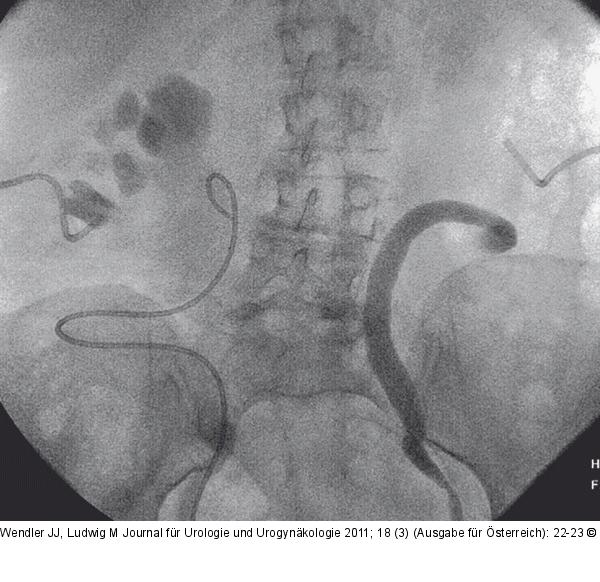

Abbildung 1b: Ureteropyelographie Retrograde Ureteropyelographie links bei liegenden PCN beidseits und liegendem JJ-Katheter rechts; Z. n. Ureteropyelographie rechts |

Retrograde Ureteropyelographie links bei liegenden PCN beidseits und liegendem JJ-Katheter rechts; Z. n. Ureteropyelographie rechts |